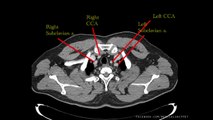

The Heart and Major Vessels - PART 1 - Anatomy Tutorial

3D anatomy tutorial on the heart and some of the major vessels in the thorax that lead to and from the heart using BioDigital Human browser (). This is a good basic tutorial to watch if you want to learn some simple but important anatomy of the cardiovascular system. I have broken the tutorial into 2 parts, so please be sure to watch both parts!\r